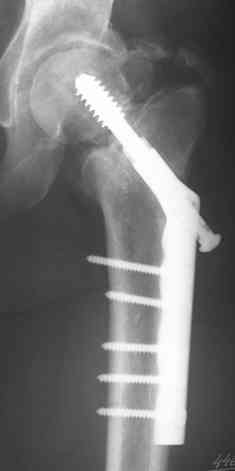

Вальгизирующая остеотомия по Marti с латерализацией, фиксация клинковой

пластиной (см. рис.) - хотя результат менее предсказуем, чем при эндпротезировании.

Поэтому отбрасывая все остальное, считаем, что Intertrochanteric valgus osteotomy или Межвертельная вальгусная остеотомия создает те необходимые биомеханические преимущества, которые восстановят измененную биомеханику.

Среди всех остальных этот вариант является менее инвазивным, отличный результат от 75-90%, отсутствует дополнительный риск повреждения кровоснабжения головки бедра, и главное - биомеханические преимущества.

Технически все делается внесуставно, без вскрытия места ложного сустава, в положение больного на спине, для облегчения работы ближе к краю операционного стола.

На вертеле делается "срез" в латеральном кортекса для клинка пластины и специальное долото вводится под 90-градусным углом к бедру по заранее приготовленному предоперационному плану.

Делается межвертельная остеотомия с удалением клина в 20-30 градусов в зависимости от шеечно-диафизарного угла, а все остальное сделает 120 градусная Blade Plate.

Для предупреждения вальгуса механической оси конечности необходима латеризация бедра, кусок кости от остеотомии, уложеный между пластиной и латеральным кортексом, латерализует бедренный диафиз.

На представленных снимках некоторые моменты, предоперационный план, латерализация, расчет длины, ориентир для введения и наборы.